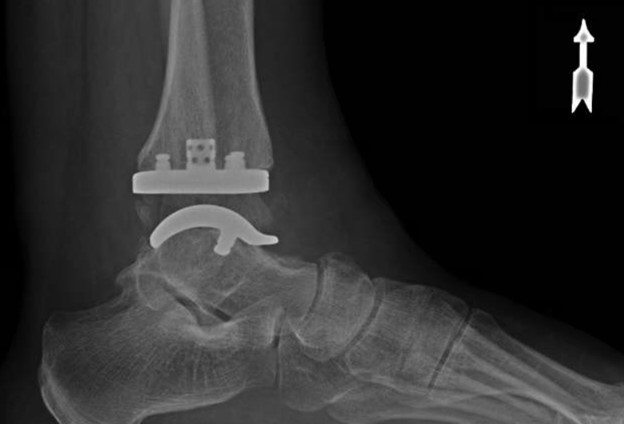

where he performed around 100 cases of total ankle arthroplasty. His other clinical interests include minimally invasive surgery and foot and ankle trauma.